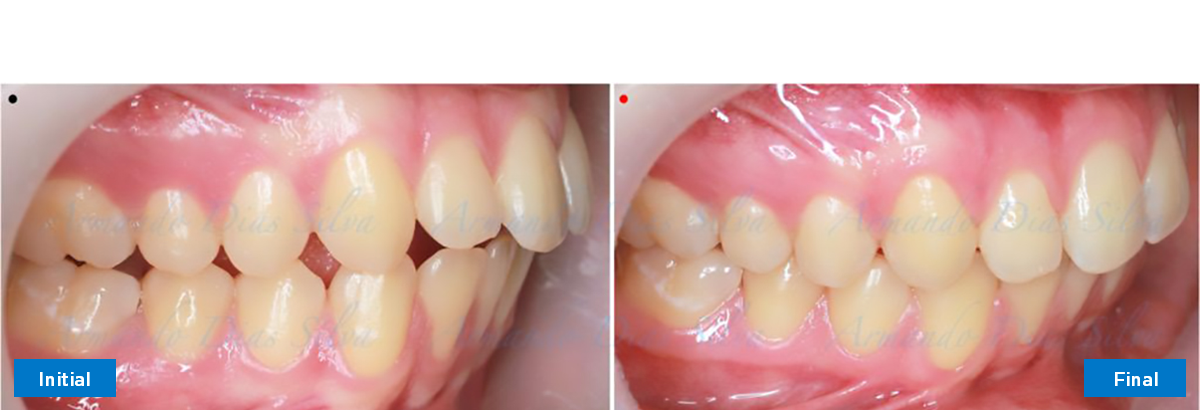

Este paciente adolescente presenta molares de Clase II y no le gusta su mordida abierta ni lo protrusivos que son sus dientes frontales. Por sus fotografías faciales, parece que su mandíbula es retrognática o le falta volumen en la barbilla. El historial del paciente también indica que existe un problema funcional al no haber guía de los incisivos.

• Molares de clase II

• Diastema

• Espaciamiento leve de las arcadas superior e inferior (deficiencia transversal de 3,45 mm)

• Incisivos superiores e inferiores proclinados

• Molares de clase I logrados con distalización y sin elásticos

• Sin expansión maxilar, respetando la envoltura periodontal

• Incisivos inferiores retroinclinados, que mejoran la estabilidad a largo plazo